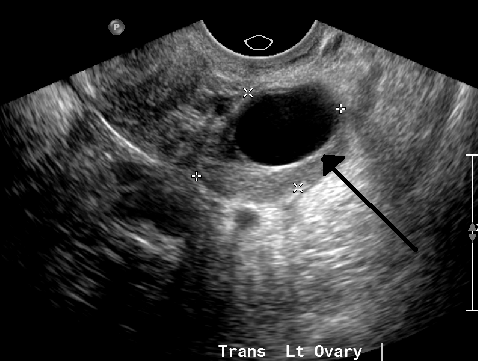

질식 초음파 검사로 촬영한 67 x 40 mm 크기의 자궁내막종으로, 다소 과립상의 내용물을 보입니다. - 난소에 생긴 자궁내막증으로 인한 것이다.

난소 낭종은 보통 초음파, CT 촬영, MRI 중 하나를 통해 진단한다.[13] 초음파는 가장 중요한 영상 기법인데, CT 촬영에서 이상 소견이 발견되더라도 초음파에서는 정상으로 나타나는 경우가 있기 때문이다.[4][6] 다른 영상 기법이 필요한 경우, MRI가 CT 촬영보다 더 신뢰할 수 있다.[4] 경험이 풍부한 초음파 검사자는 대개 양성 난소 낭종을 쉽게 식별할 수 있으며, 다른 접근 방식에 필적하는 정확도를 보이기도 한다.[4]